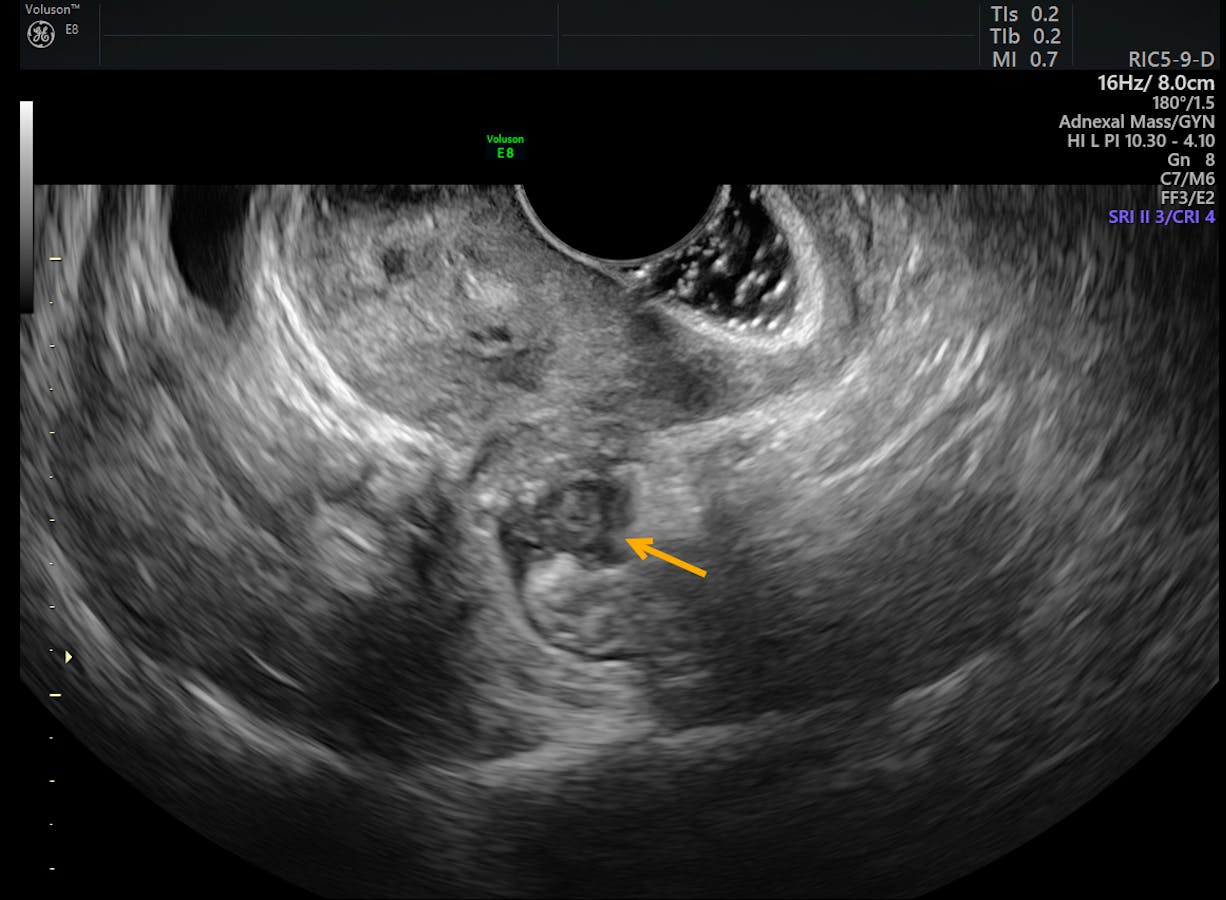

Noninvasive ultrasound diagnosis of endometriosis Contemporary OB/GYN Endometriosis Lesion Learn about the symptoms, causes, stages, diagnosis, complications, and treatment options for endometriosis. Superficial peritoneal endometriosis (accounting for around 80% of. endometriosis is a disorder in which tissue similar to the lining of your uterus grows outside of your uterine cavity. according to their physiopathology and their localization, ectopic endometrial lesions, consisting of. Outside the uterus, the tissue. Endometriosis Lesion.

Transvaginal US of Endometriosis Looking Beyond the Endometrioma with Endometriosis Lesion Outside the uterus, the tissue thickens and bleeds, just as typical endometrial tissue does during menstrual cycles. according to their physiopathology and their localization, ectopic endometrial lesions, consisting of. Superficial peritoneal endometriosis (accounting for around 80% of. several lesion types have been described: Learn about the symptoms, causes, stages, diagnosis, complications, and treatment options for endometriosis. Superficial endometriosis. Endometriosis Lesion.